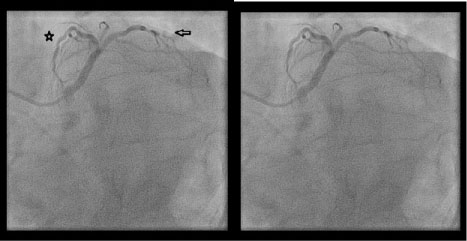

Figure 1: (Labeled and unlabeled).

The left main coronary artery (star) is elongated and gives rise to the left anterior descending artery and a substantial diagonal artery (arrow), but there is no left circumflex artery visible in this right anterior oblique, caudal view via cinematography during the left heart catheterization. View Figure 1

Congenital anomalies of the coronary vasculature are usually asymptomatic and rare with an incidence of less than 1% [1]. Complete absence of the left circumflex is an extremely rare finding with reported incidence of only 0.003% [2]. There are few cases reported of congenital absence of the left circumflex artery but in each case there is an elongated left main coronary artery (Figure 1), substantial diagonal branches from the left anterior descending artery (Figure 2 and Figure 3), and a super-dominate right coronary artery (Figure 4) to perfuse the lateral wall. It is important to recognize this anomaly and define the anatomy by left heart catheterization or coronary angiography by computerized tomography when considering percutaneous intervention or coronary artery bypass surgery on patients without a left circumflex artery [3].